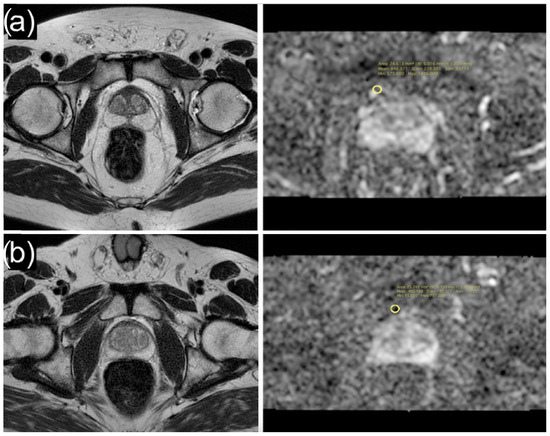

2.2. MRI Acquisition

| Periprostatic adipose tissue ADC | 876 (654, 1112) | 1003 (773, 1299) | 972 (559, 1103) | 656 (455, 952) | <0.001 |